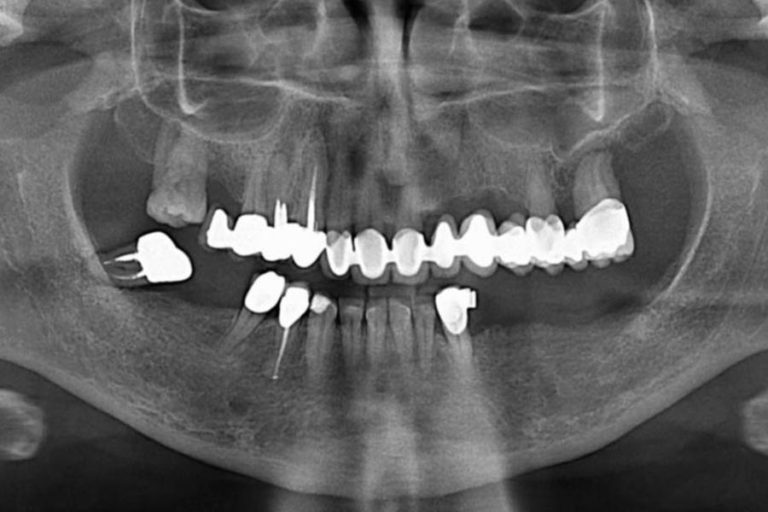

La gengivite e la parodontite sono malattie delle gengive e dei tessuti che circondano e supportano i denti e sono causate dai batteri contenuti nella placca e nel tartaro.